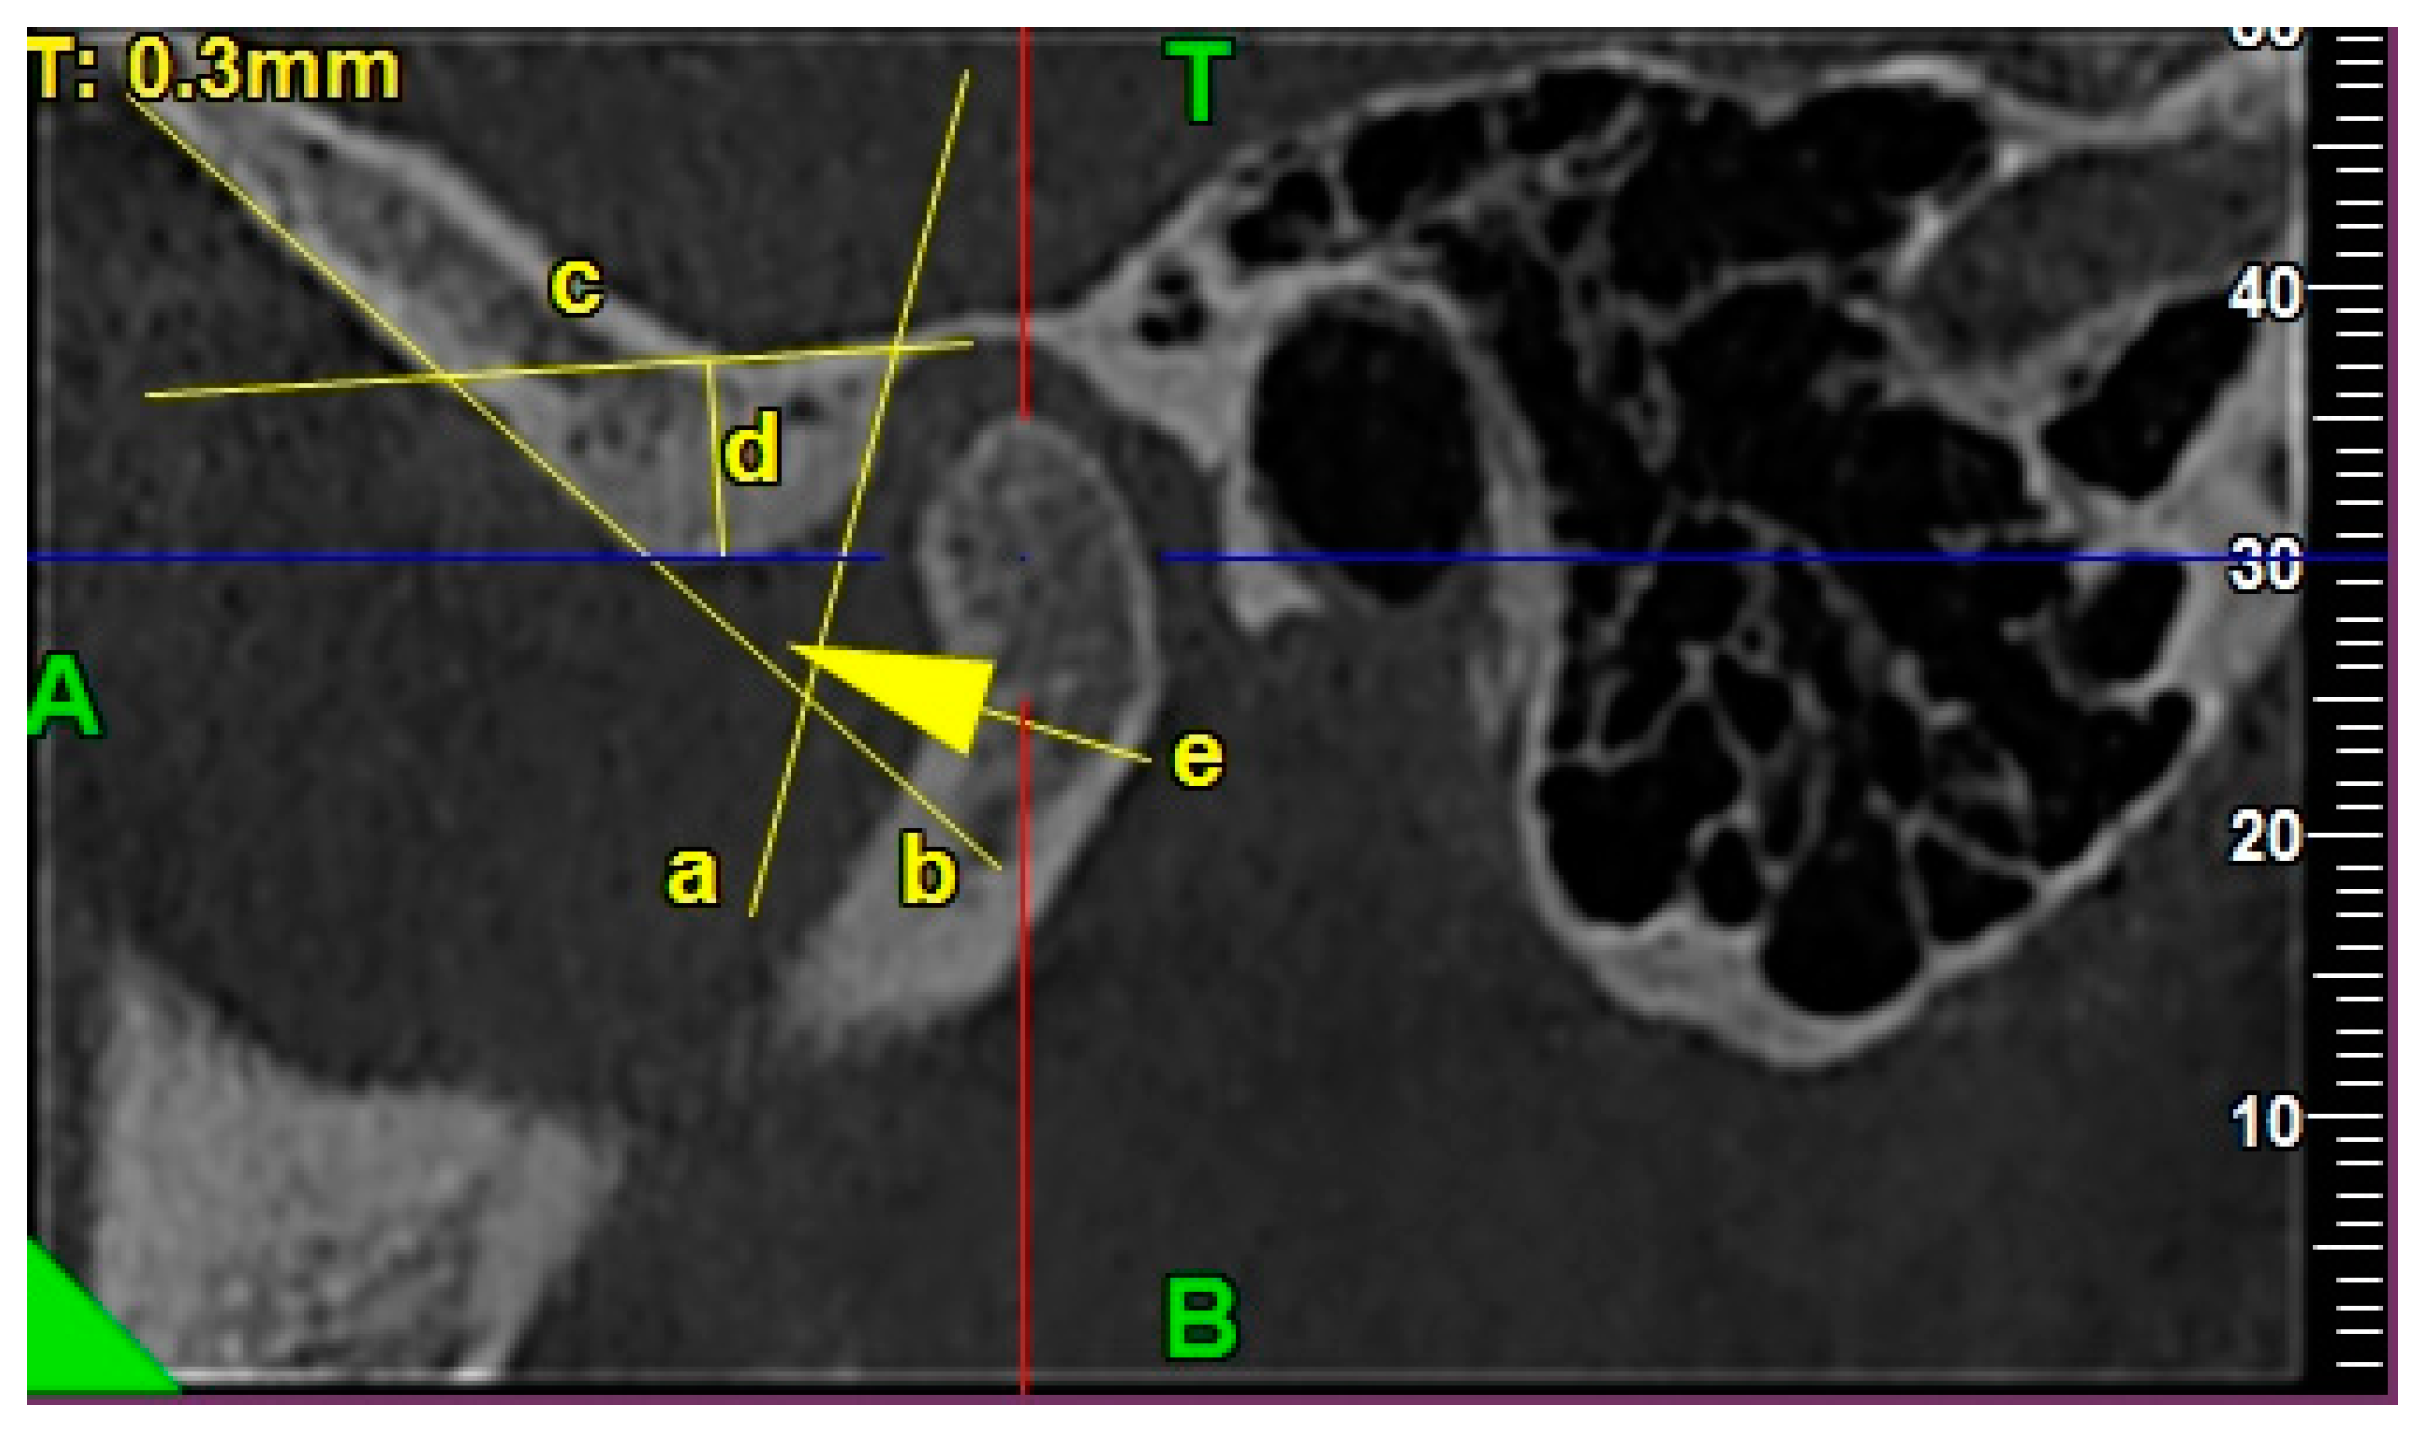

2.4.3. Morphology of the Articular Eminence

2.4.4. Assessment of the Anterior, Posterior, and Superior Joint Spaces

2.4.5. Assessment of the Sagittal Position of the Condyle

- P—posterior joint space,

- A—anterior joint space.